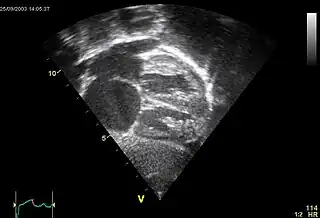

Comunicación interauricular

La comunicación interauricular (CIA) es una cardiopatía de origen congénito acianógena (sin cianosis), consistente en una deficiencia del septum o tabique que separa las cavidades del corazón denominadas aurículas y que resulta en una libre comunicación entre el lado derecho e izquierdo de las aurículas. Puede estar situada en cualquier parte del mismo, siendo su localización más frecuente en la región de la fosa oval y así se denomina tipo ostium secundum.

![]() CIA (ostium secundum) | ||